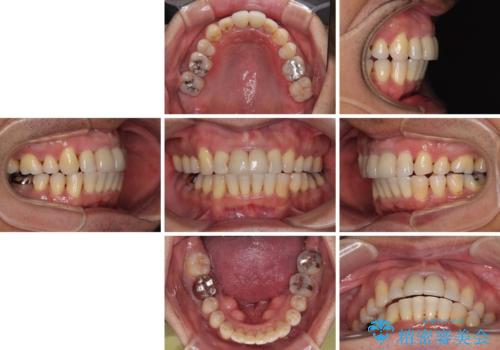

上顎前歯に装着されていた保険診療の前歯は見た目が気になるとのことであったので、矯正治療後にオールセラミッククラウンにて補綴治療を行うこととしました。

食いしばりにより奥歯がすり減っており、咬み合わせが定まるまで時間がかかりましたが、整った口もに仕上がりました。